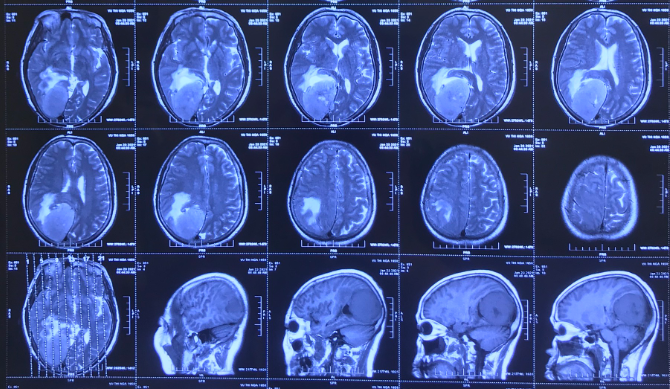

Vai trò của MRI trong chẩn đoán u màng não là tạo ra hình ảnh rõ ràng về vị trí, kích thước và tính chất của u. MRI có độ phân giải cao hơn so với các phương pháp chẩn đoán hình ảnh khác như CT scan, cho phép các bác sĩ và chuyên gia y tế nhìn thấy chi tiết nhỏ hơn của u màng não.

Ngoài ra, MRI cũng cho phép bác sĩ đánh giá mức độ tổn thương của các mô xung quanh u màng não và xác định liệu u có lan sang các vùng khác của não hay không. Điều này rất quan trọng trong việc quyết định liệu phẫu thuật là cách tốt nhất để điều trị u màng não hay không.